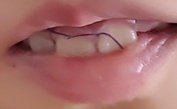

우는 아이 입안에는 검정 실밥과 스플린트 안쪽 피가 보였어요

어쨌든 이제 수술은 끝. 과잉치 안녕-

잘 아물기만 하면 되니 조금만 더 힘내 보아요

과잉치 발치 수술 일주일 후

이제 약속한 날짜에 다시 병원으로 가서 실밥 제거하고 끝.

과잉치 발치 수술은 이제 진짜 끝.

왠지 앞니도 더 가지런해진 것 같은 느낌(또는 착각)이 들기도 해요